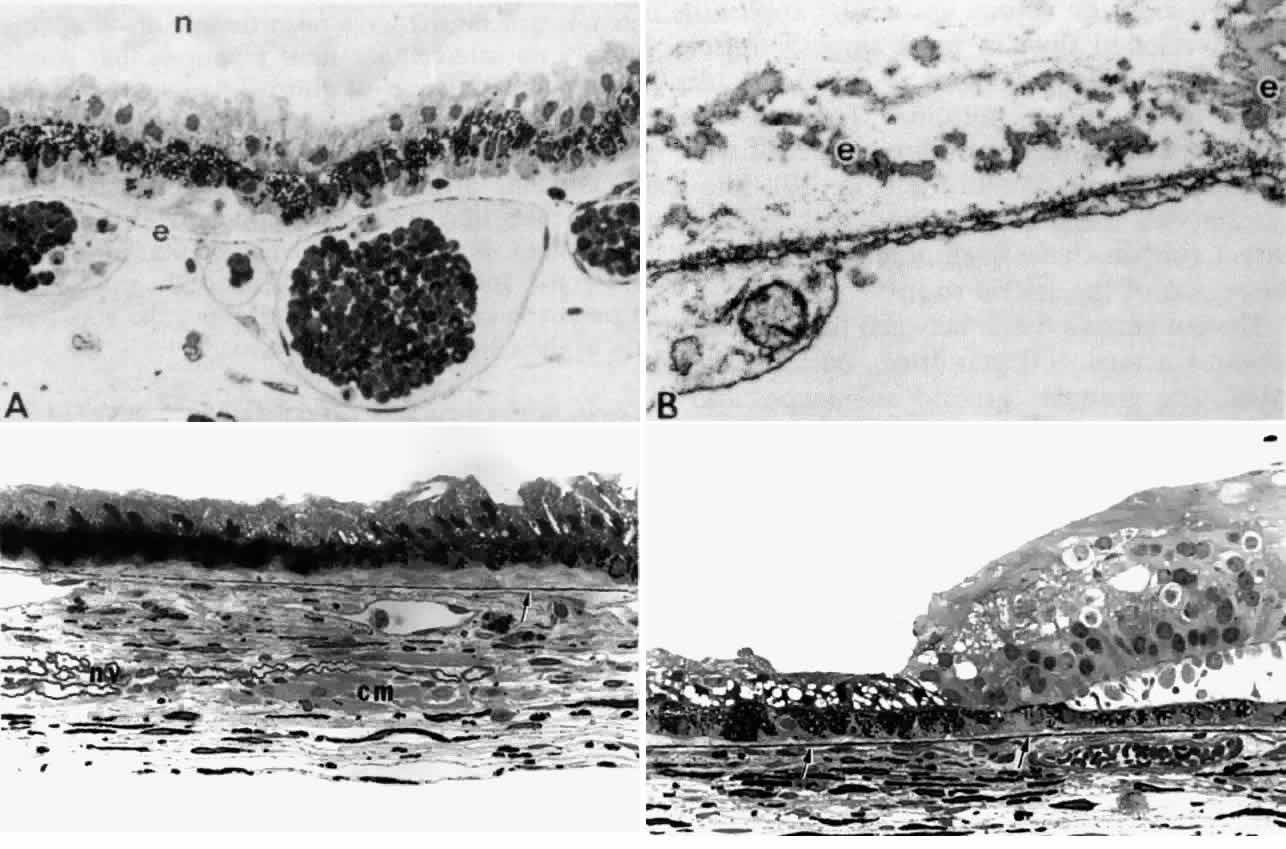

The choriocapillaris does not continue forward into the ciliary body from

the choroid, but a thin layer of elastica continuous with Bruch's

membrane does (Fig. 31D). In the ciliary body, the elastica quickly becomes separated from the

basement membrane of the ciliary PE by the interposition of a dense and

then looser connective tissue (Fig. 31C). The elastic layer remains close to the underlying thin-walled pars plana

veins (Fig. 31A), becoming increasingly discontinuous (Fig. 31B) with wider branching, and is finally lost under the pars plicata.  Fig. 31. Bruch's membrane in the ciliary body. A. In mid pars plana, Bruch's

elastica is a dotted thin line (e), appearing continuous with vein

walls. n, zonular bundles. (Toluidine blue, X 400) B. The dotted line

is a network of small elastic fibers with homogeneous elastin cores (e), outside

the fenestrated capillary wall. (Alcian blue, X 24,500) C. Elastica

becomes thicker and more complete (arrow) further posteriorly

in pars plana. Note nerve bundles (nv) and ciliary muscle bundles (cm) in

stroma. (Toluidine blue, X 433) D. Elastica continues smoothly

from end of pars plana (left arrow) into peripheral choroid (right arrow). (Toluidine

blue, X 433) Fig. 31. Bruch's membrane in the ciliary body. A. In mid pars plana, Bruch's

elastica is a dotted thin line (e), appearing continuous with vein

walls. n, zonular bundles. (Toluidine blue, X 400) B. The dotted line

is a network of small elastic fibers with homogeneous elastin cores (e), outside

the fenestrated capillary wall. (Alcian blue, X 24,500) C. Elastica

becomes thicker and more complete (arrow) further posteriorly

in pars plana. Note nerve bundles (nv) and ciliary muscle bundles (cm) in

stroma. (Toluidine blue, X 433) D. Elastica continues smoothly

from end of pars plana (left arrow) into peripheral choroid (right arrow). (Toluidine

blue, X 433)

|